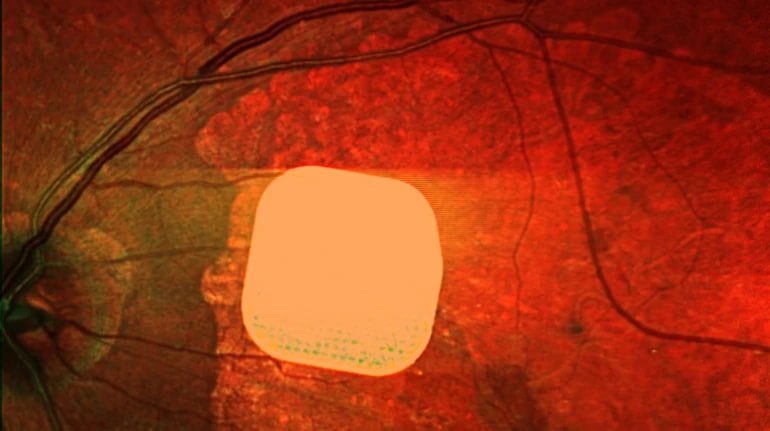

Британські лікарі успішно випробували новий електронний імплант Prima, який допомагає відновити частково зір у пацієнтів із макулодистрофією, що є головною причиною втрати зору у людей після 50 років. Мікрочип розміром 2×2 мм встановлюється під сітківку ока і підключається до системи окулярів доповненої реальності. Ця технологія дозволяє пацієнтам знову розрізняти літери та слова після періоду адаптації. Лікарі вважають, що імплант Prima може значно покращити якість життя людей із важкими зоровими порушеннями, надаючи їм можливість читати та бути більш незалежними.